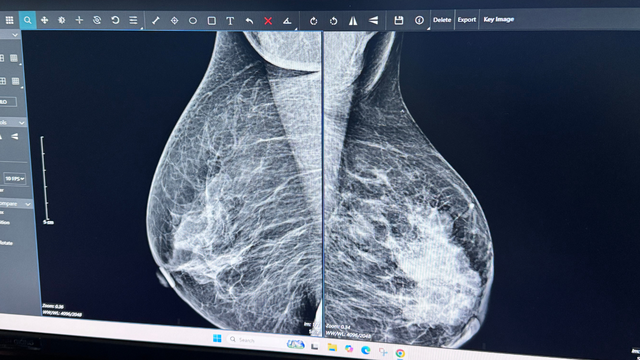

Hình ảnh chụp X-quang tuyến vú giúp bác sĩ phát hiện sớm các tổn thương nghi ngờ ung thư vú.

Trải qua nhiều năm làm nghề, điều bác sĩ Thùy Trang luôn nhắc đến là tầm quan trọng của việc tầm soát sớm ung thư vú. “Ung thư vú, nếu phát hiện sớm, hoàn toàn có thể điều trị thành công. Sự chủ động của người phụ nữ chính là yếu tố quan trọng nhất để bảo vệ sức khỏe và hạnh phúc gia đình”, BS Trang nhấn mạnh.

Bác sĩ Trang khuyến nghị, phụ nữ nên siêu âm hoặc chụp X-quang tuyến vú định kỳ, đặc biệt khi có dấu hiệu bất thường. Đây là cách đơn giản nhưng hiệu quả để phát hiện sớm, tránh những tiếc nuối muộn màng.